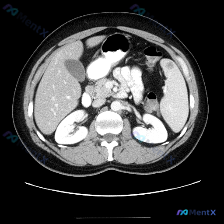

看到一份腹部CT的单层面影像,用户直接问“这个图像里有什么特异性异常?脾脏病变”。一开始我也预设“可能有问题”,但仔细阅片并看完分析后,觉得这个病例的思维过程特别值得分享。 --- 先整理一下这份影像的核心事实 这份是上腹部层面的横断面CT,影像质量良好: 肝脏:形态大小可,实质密度均匀,未见明确占...

看到一个资料,问题直接指向「脾脏病变」,附上了一张腹部增强CT的横断面图像。整理一下读片和分析思路,这个病例的核心其实不是「找病变」,而是「怎么面对阴性结果」。 病例影像基础信息 - 检查手段:腹部CT横断面,软组织窗 - 增强状态:根据血管及实质强化,考虑为静脉期/平衡期 - 扫描层面:上腹部,包...